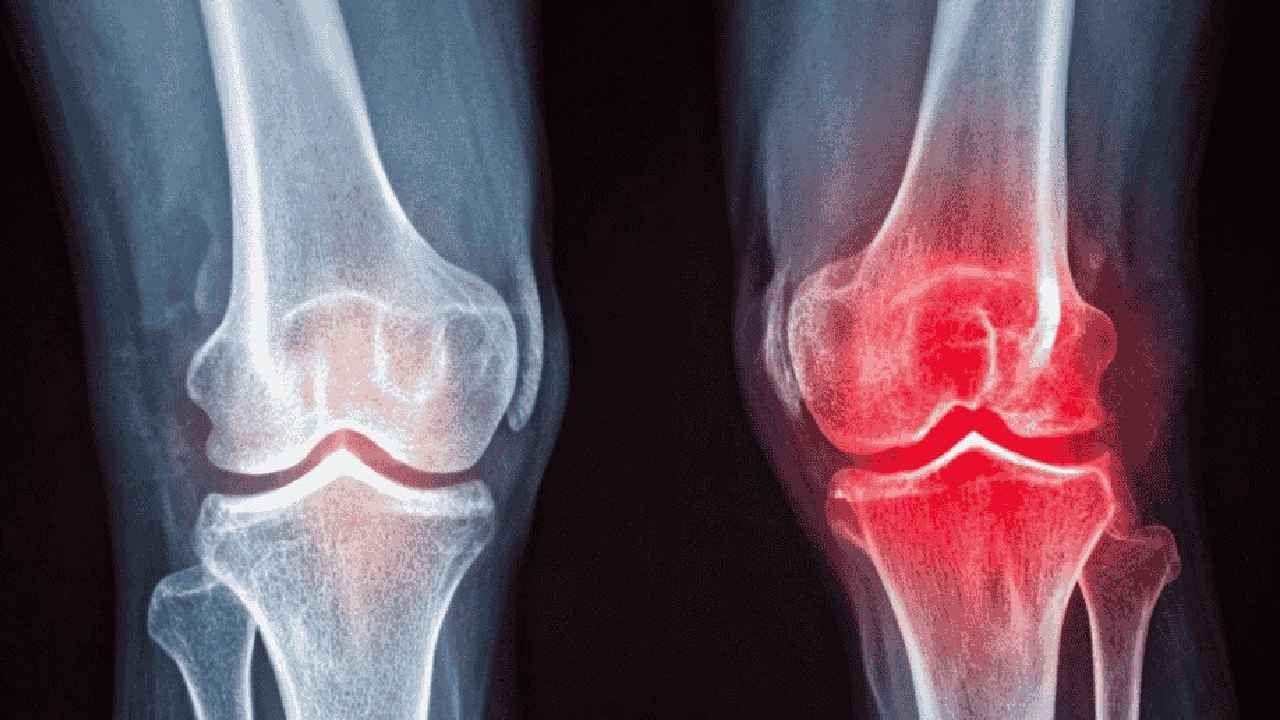

Günümüzde milyonlarca insanı etkileyen diz kireçlenmesi (gonartroz), günlük yaşam kalitesini ciddi şekilde düşüren bir sağlık sorunu. Merdiven çıkarken, yürürken ve hatta dinlenirken hissedilen ağrı, birçok hastayı "Acaba ameliyat şart mı?" sorusuyla baş başa bırakıyor. Ancak modern tıp, diz protezi ameliyatını son evreye saklayarak, hastaların büyük çoğunluğuna ameliyatsız çözüm yolları sunuyor.

Diz kireçlenmesinde başarı, tek bir iğneye veya ilaca bağlı değildir. Başarı; doğru tanı (kireçlenmenin evresi), hastanın yaşam tarzı değişiklikleri (kilo kontrolü gibi), "olmazsa olmaz" olan sistematik kas güçlendirmesi ve gerektiğinde ultrason eşliğinde uygulanan modern enjeksiyonların doğru kombinasyonundan gelir.

Son evre (Evre 4) kireçlenmede kalıcı çözüm diz protezi ameliyatı olsa da, hastaların büyük çoğunluğu için ameliyatsız, konforlu ve aktif bir yaşam sürmek mümkündür.